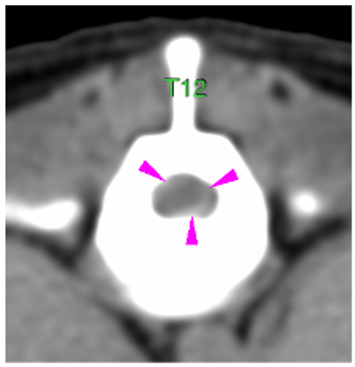

Inmediatamente caudal a la lesión descrita, a nivel craneal del cuerpo vertebral de T12, se visualiza una leve cantidad de material hiperatenuante a la médula pre-contraste que la rodea (flechas rosas)